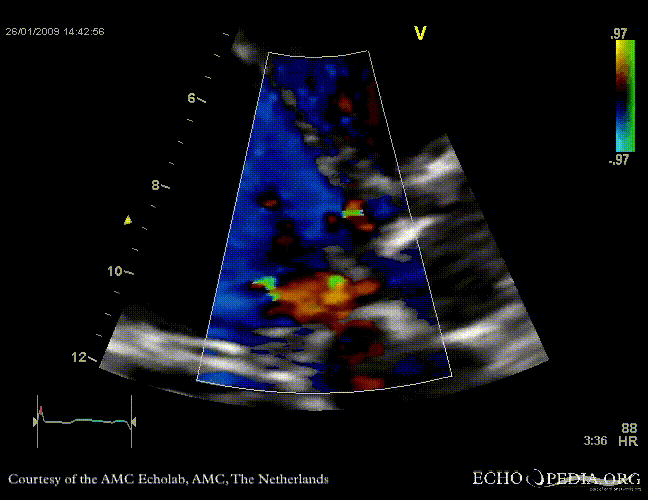

Aortic valve endocarditis with vegetation

Case description: This patient had endocarditis with an aortic valve vegetation

E00120.gif

A5CH aortic valve vegetation Aortic valve regurgitation jet